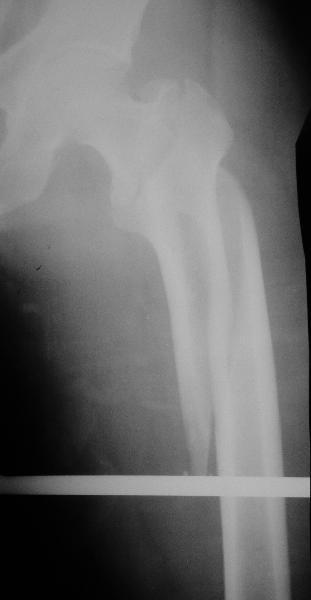

В диагноз пишем... Потом же как-то анализировать надо. Что-то никто не откликнулся на этот вопрос из англоязычных коллег. Все-таки - как такой перелом надо классифицировать? А если шейка бедра + диафиз? Завтра покажу такой случай.

DK> Какой метод выбрали для фиксации,

Реконструкционный гвоздь.